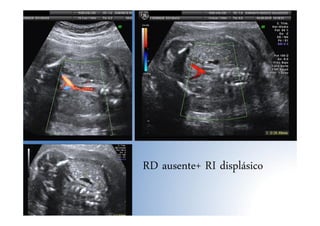

• Agenesia renal unilateral: pronóstico excelente. Buscar riñón

pélvico.

• Displasias renales

– DR multiquística: 80% unilaterales, 2ª anomalía de la vía

urinaria tras hidronefrosis, quistes de diversos tamaños no

comunicados, pueden 3º T, DD hidronefrosis

RD ausente+ RI displásico

RD ausente+ RIdisplásico